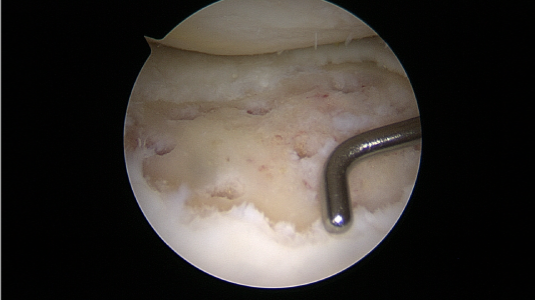

미세천공술

피부에 상처가 나면 스스로 치유되는 이유는 혈액 속 상처를 치유하는 재생인자가 있기 때문입니다. 그러나 연골에는 혈관이 없어 손상되더라도 스스로 치유하는 능력이 없습니다.

미세천공술은 관절내시경 수술을 통해 연골에 3mm 간격으로 4mm 정도의 작은 구멍들을 의도적으로 내어 출혈을 유도하고 골수를 자극하며 연골이 재생될 수 있도록 하는 치료법입니다.

□ 이전부터 시행되고 있는 재생 치료로, ‘섬유성 연골’로 재생

□ 관절내시경을 통해 시행되어 절개가 작고 부담이 적음

□ 출혈이나 부작용이 거의 없으며 조직 손상이 적음

□ 시행 후 회복이 빠르고 통증이 적음